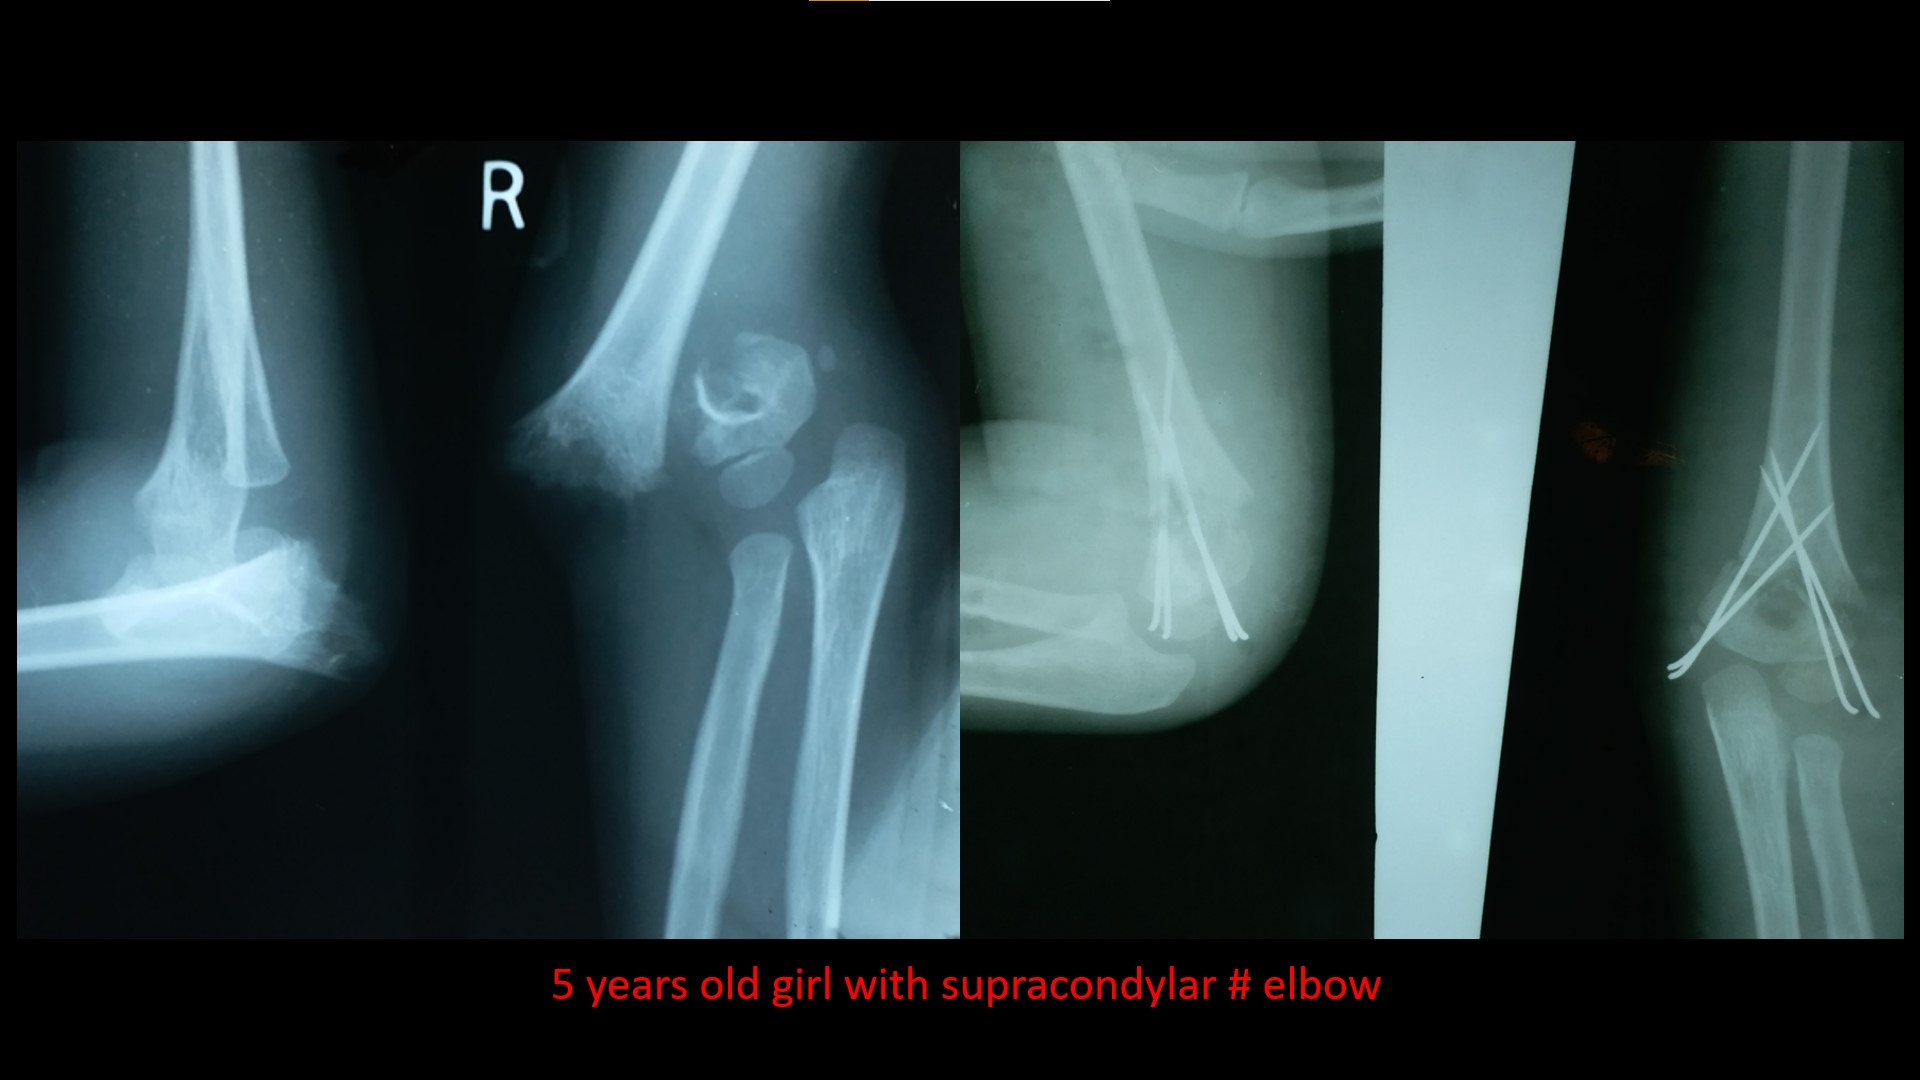

SUPRACONDYLAR #